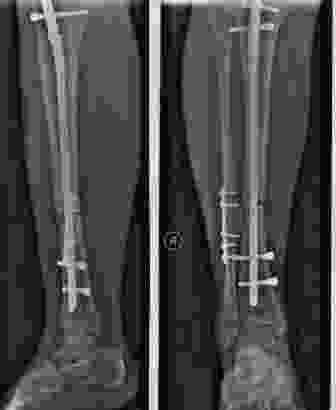

只有经历过的人才能体会到那种漫长的愈合过程,胫腓骨下三分之一段骨折,是人体少有的,最难愈合的部位之一。其它部位骨折,一般有6~8周骨痂就形成了,可以慢慢开始下地负重,但是这个位置骨折,往往四五个月,甚至半年了都不长骨痂,临床上,甚至有骨不愈合的情况出现,最终不得不接受二次植骨手术。

人体组织的愈合意味着这个位置要有血液供应,胫腓骨下三分之一段骨折会破坏局部的滋养血管,从而导致这个部位很难愈合。所以,这种类型骨折一般会采用髓内钉固定,一方面是比较稳定,另一方面就是考虑减少破坏骨折部位的血液供应。